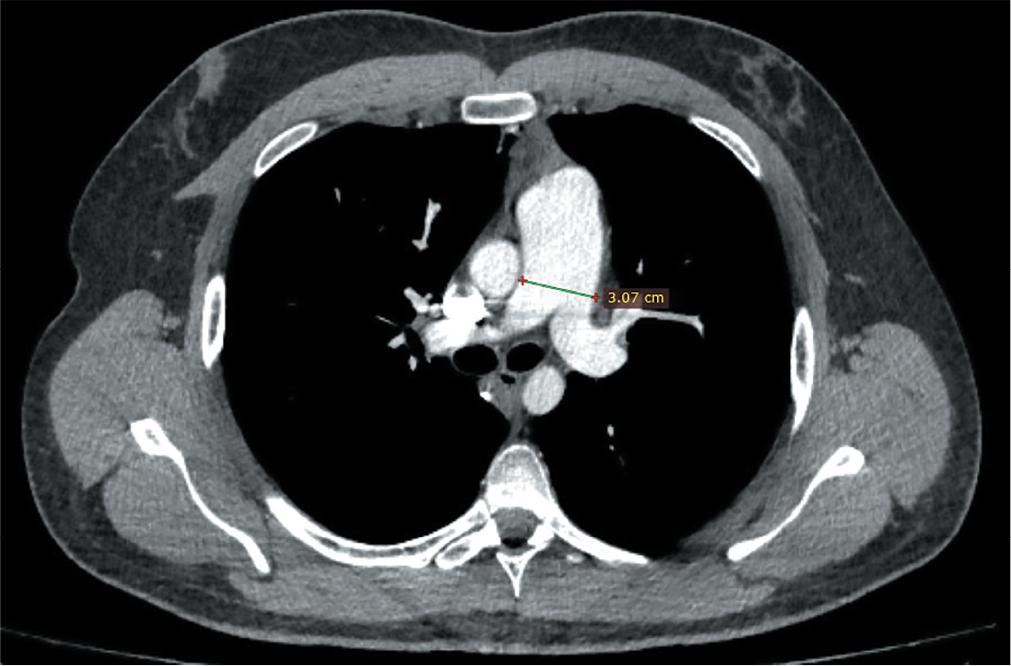

On contrast-enhanced chest CT (Computed Tomography), a major pulmonary artery dilation and dilated right heart were observed, without pulmonary embolism and changes in the pulmonary parenchyma. Neither transthoracic echocardiography nor CT examination revealed congenital heart diseases (Figures 3 and 4).

Contrast-enhanced chest CT scan transversal sections showing evidence of major dilation of the pulmonary arterial trunk.